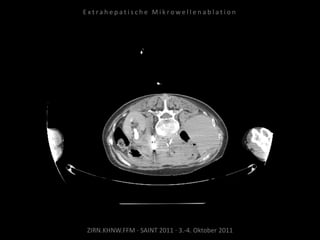

Bildgebung vor MWA:

CT 14.03.2011

Situation:

Nur 1 Metastase, diese ist jedoch

progredient. Kritische Lage in

Herznähe.